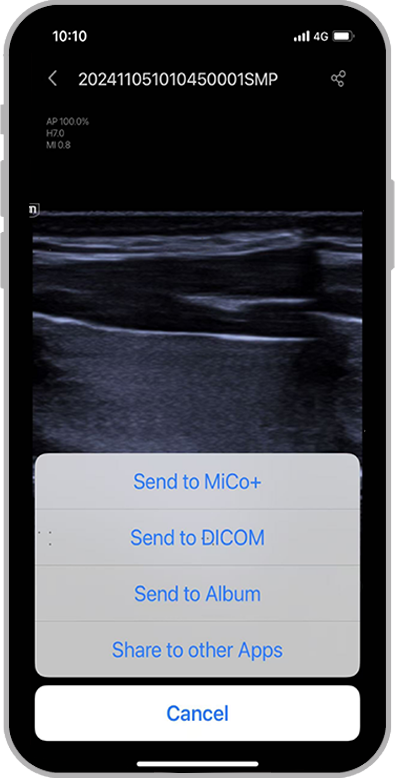

1Facile da usare, con un'interfaccia utente intuitiva

2Migliora l'efficienza grazie alla possibilitĂ di utilizzo con una sola mano

3Offre soluzioni per la gestione dei dati dei pazienti

4Completa il flusso di lavoro grazie alla perfetta interconnessione con il sistema informativo